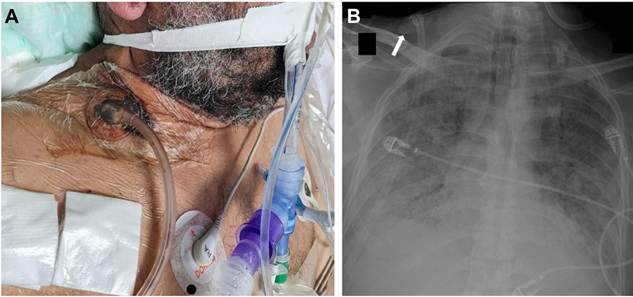

Algunos pacientes con perforaciones iatrogénicas de la tráquea pueden ser tratados de forma conservadora, pero si el paciente requiere ventilación mecánica este abordaje terapéutico está contraindicado 2,3. Debido al estado crítico del paciente, la reparación quirúrgica no era una opción viable, por lo que se decidió manejar con terapia de presión negativa. El sistema de presión negativa se colocó en la región supraclavicular derecha (Figura 3A) logrando un resultado muy favorable, con lo cual al tercer día se pudo retirar el vasopresor, observando además la resolución completa del enfisema subcutáneo y una significativa disminución del neumomediastino (Figura 3B).